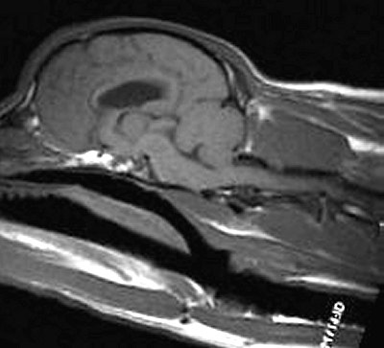

8 years old

No symptoms of SM whatsoever

Very mild malformation, slight

squashing/pinching of cerebellum

No herniation

Medulla almost normal

Very slight dilatation of central canal

in one tiny area